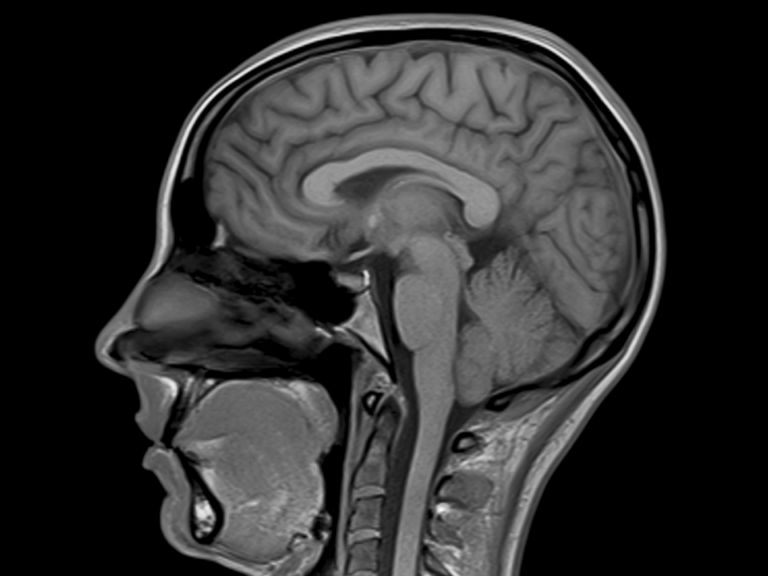

MRI Brain With Contrast? What It Is, Purpose, Procedure and Results Do Mri With Contrast Hurt Contrast agents, while generally safe, carry the risk of allergic reactions and, in rare cases, nephrogenic systemic fibrosis (nsf) in patients with severe renal impairment. What to expect during an mri with contrast. According to a 2016 review. When they do occur, they are often mild — common side effects include hives and a rash. The contrast agent is administered. Do Mri With Contrast Hurt.